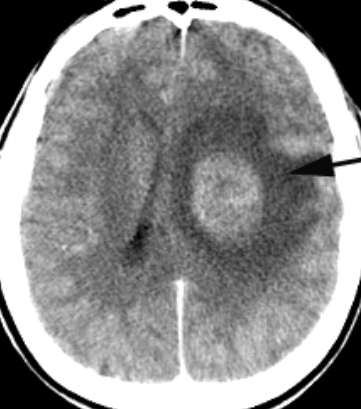

Figura 1. Imagem de uma TC com contraste de tumor acompanhado de edema cerebral em um caso de HIC parenquimatosa (IENCEAN, 2018)

Na Hipertensão intracraniana parenquimatosa, a alteração da pressão é precedida pelo aumento de volume intracraniano por razões expansivas, compressivas, hipóxia ou edema pós-traumático. Os principais processos expansivos têm como causas tumores, abscessos e hematomas. Nos últimos anos, com a incorporação de novas drogas (terapias-alvo, imunoterapia), tem-se observado aumento da sobrevida dos pacientes oncológicos. No entanto, a maior parte das drogas oncológicas não ultrapassa a barreira hematoencefálica (BHE), sendo assim considerado o tecido cerebral um santuário, onde muitas vezes tem-se o controle da doença sistêmica e a progressão de doença a nível de sistema nervoso central. (NOLAN, 2018)